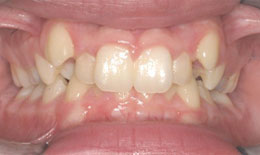

• Deep bite with protruding cuspids